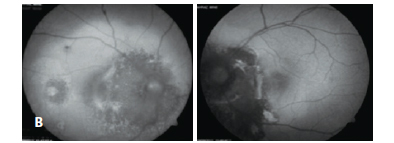

A 28-year-old woman presented with visual loss in the right eye (RE), which was ongoing for 10 days. Her visual acuities were 20/400 in RE and 20/25 in the left. Intraocular pressures were 12 mmHg and 14 mmHg respectively. Anterior segment findings were unremarkable. Fundus examination revealed an orange central fovea (calcified area) surrounded temporally and nasally by a yellow-white region (decalcified area). Her LE fundoscopic exam showed the atrophic choriocapillaris nasal to the disc, a decalcified area between the disc and the fovea, and a calcified area temporally (Figure 1A).

We observed a cage-like reflective pattern with the EDI OCT, which corresponds to the calcified region of the choroidal osteoma (Figure 2A). In some regions, a hyper-reflective band was visible between the calcified tumor tissue and unaffected choroid (Figure 3). The retinal tissue covering the calcified areas seemed intact (Figure 2, 3). FAF imaging of the calcified areas showed slight hyperautofluorescence indicating the integrity of RPE (Figure 1B).

We described three different reflectivity patterns in the decalcified area. First one was a thick hump-like hyper-reflective band, which had posterior acoustic shadowing and had a non-intact RPE overlying it (Choroidal neovascular membrane - CNVM) (Figure 2B). The outer retinal structures (RPE, IS-OS line and external limiting membrane) of the second pattern were disintegrated, the tumor plane was irregular and the vascular structures of the tumor were visible. In addition, the second pattern showed less acoustic shadowing compared to the first one. The third pattern was an irregular hyper-reflective pattern partially beneath or over the RPE and Bruch membrane. In FAF imaging, decalcified areas were mostly hypoautofluorescent although showed hyperautofluorescence in some parts (Figure 1C).

Choroidal thickness was increased in the RE, which had choroidal neovascularization. In addition, intra and subretinal serous fluid was observed. Outer segment elongations similar to the ones in central serous chorioretinopathy (CSCR) were evident. Hyperautofluorescence spots were evident in FAF imaging which correspond to the areas of serous fluid (Figure 1B).